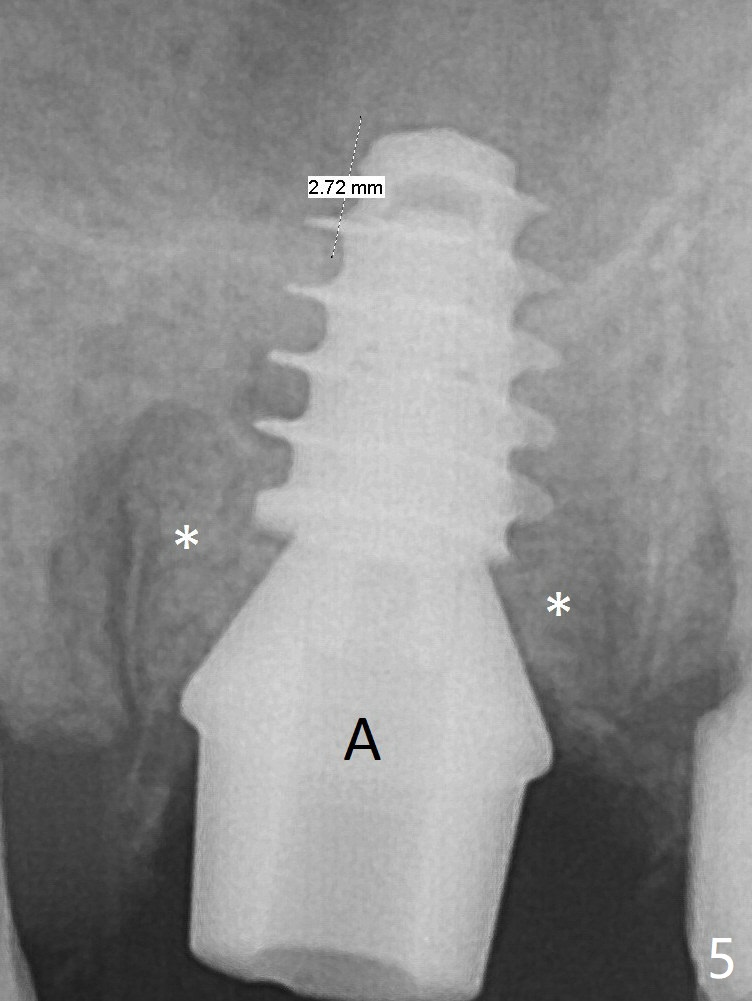

Finally a 5.5x7 mm IBS implant is placed with 30 Ncm (Fig.5).  After placement of Osteogen plug in the apical portion of the sockets, allograft/Osteogen is placed in the remaining sockets (Fig. 5 *).  The latter is partially contained by a 6.5x4(3) mm abutment (A) and ultimately by an immediate provisional.